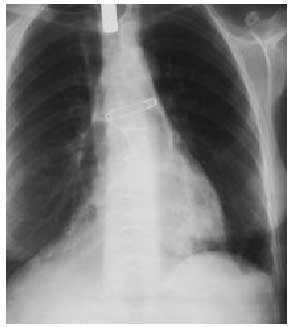

En la radiografía de tórax no se observó condensación de campos pulmonares, presentando en la proyección posteroanterior, en el borde cardíaco derecho, una imagen hidroaérea en la que se aprecian haustras, todo ello compatible con el intestino grueso (figs. 1 y 2).

Fig. 2. Imagen radiológica en proyección lateral de tórax.

Presentamos la imagen radiológica de un enfisema mediastínico, o neumomediastino si nos atenemos a su definición (presencia de aire en el mediastino), que en una rápida valoración puede resultar desconcertante, y que una completa anamnesis resuelve cualquier duda. El neumomediastino es una entidad muy poco frecuente; suele ser secundario a traumatismos, maniobras iatrogénicas y de tipo espontáneo, cuando no se haya una causa desencadenante evidente, siendo el 25% de los casos de tipo idiopático.

El diagnóstico es fundamentalmente radiológico en el tórax, en las imágenes posteroranterior y lateral, pues en ellas se aprecia mejor el aire mediastínico. Hamma insiste en el hecho de que radiológicamente pueden estar asociados neumotórax espontáneo y de mediastino, por lo que la búsqueda del enfisema mediastínico debe ser sistemática, especialmente en los izquierdos. Otro signo radiológico importante es el hallazgo de aire en los músculos cervicales, por lo que realizar una radiografía de cuello será imprescindible en todo caso sospechoso de enfisema mediastínico agudo, así como en los traumatismos torácicos que cursen con neumotórax.